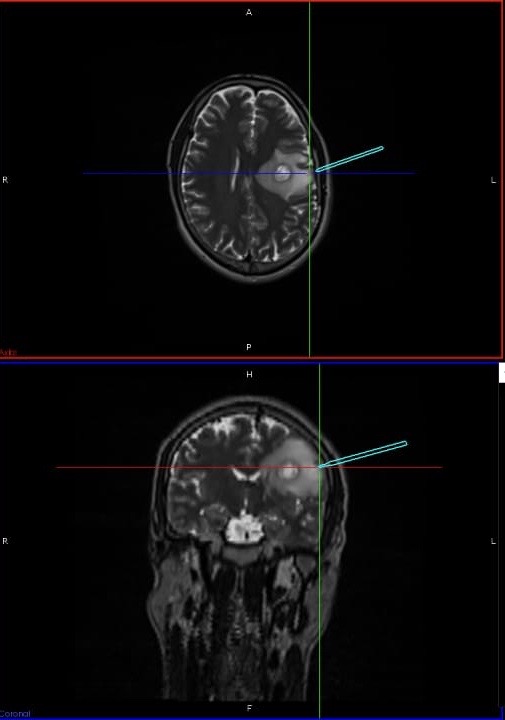

Ring enhancing lesion

Tracker showing exact point of entry

The patient had a sudden onset difficulty in speaking for 2 days. The MRI showed a ring-enhancing lesion in the left brain where the speech center is located. Differential diagnosis included a pus collection called abscess and a remote possibility of cancer. An abscess can be formed due to TB or any other type of brain infection and the treatment would vary accordingly. If the patient is not considered for the aggressive approach of surgery, I would have to consider the following two conservative approaches along with their aftereffects:

Minimally invasive image-guided neurosurgery is the option I chose for the patient. This advanced modality gives a precise entry point to tap the abscess. Surgery was performed taking adequate precautions against potential infections. An incision of 3-4 inches was made at the designated position and 7-10 ml of the thick abscess was obtained area and sent for study. Within 24 hours’ diagnosis of TB was confirmed.